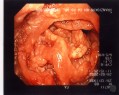

Colonkarzinom Coecalpol